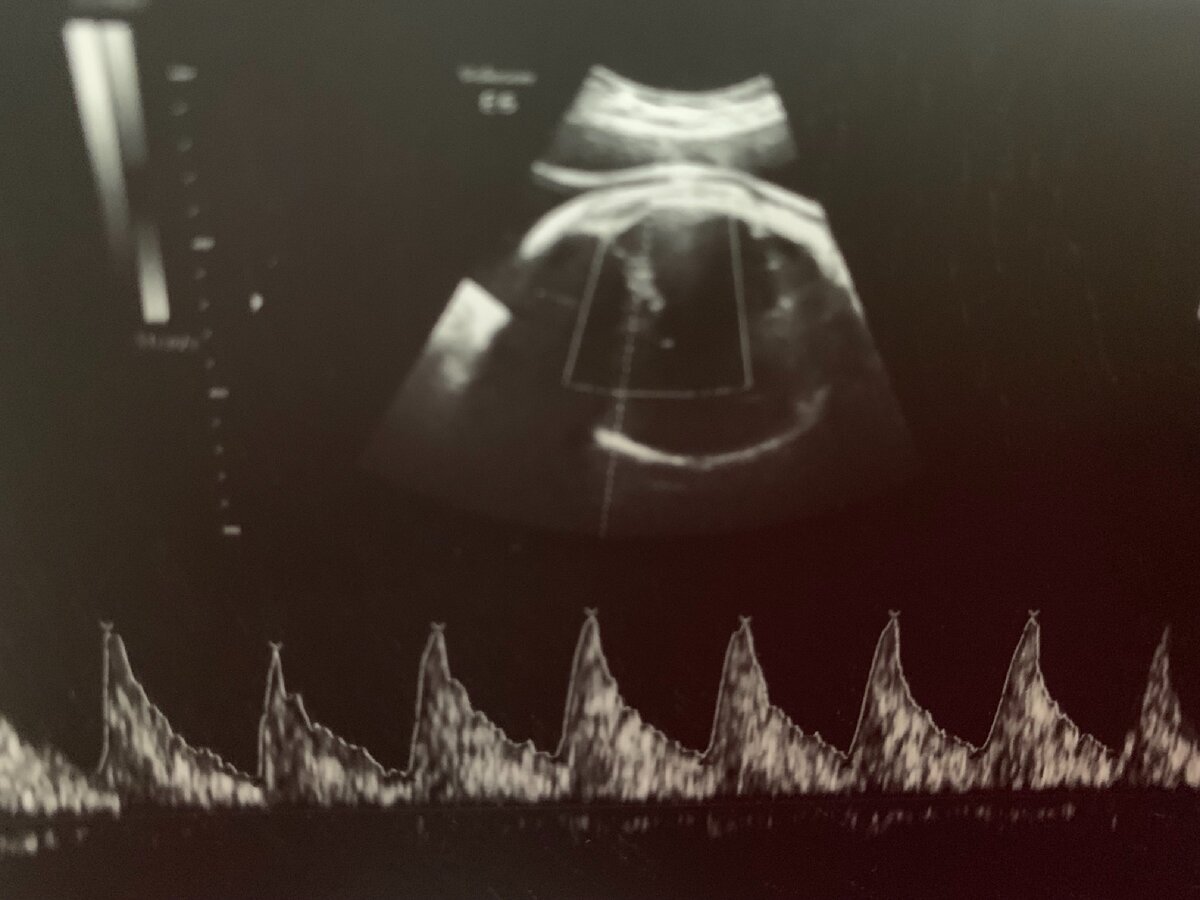

Во втором и третьем триместрах беременности чаще всего обнаруживают следующие «малые» маркеры хромосомной аномалии: гиперэхогенный кишечник, гиперэхогенный фокус в сердце, кисты сосудистых сплетений головного мозга, расширение лоханки почки, единственная артерия пуповины, многоводие.

Пример УЗ-протокола оценки маркеров хромосомной аномалии плода.

Обнаружение на УЗИ задержки внутриутробного развития, укорочения трубчатых костей, расширения желудочков мозга, трикуспидальной регургитации в сердце, аномалии стоп и кистей требует консультации генетика и решения вопроса о необходимости инвазивной диагностики.